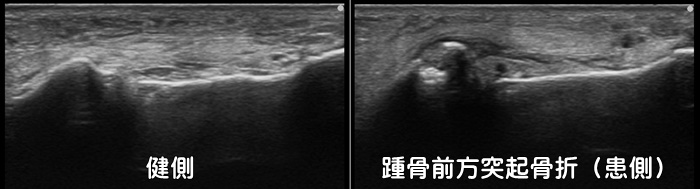

踵骨前方突起骨折・二分靭帯損傷

足首の捻挫では一般的には前距腓靭帯が損傷しますが、場合によっては二分靭帯と呼ばれる靭帯を損傷します。更に二分靭帯に引っ張られるように踵骨前方突起と呼ばれる骨の出っ張りが裂離骨折を起こす事もあります。レントゲンではなかなか見つけづらく、骨には異常なしと診断される事が多々あります。CTでは確実に診断できますが、足首の捻挫で初めからCTを撮影することは稀で、エコー検査であれば簡単に描出することが可能です。